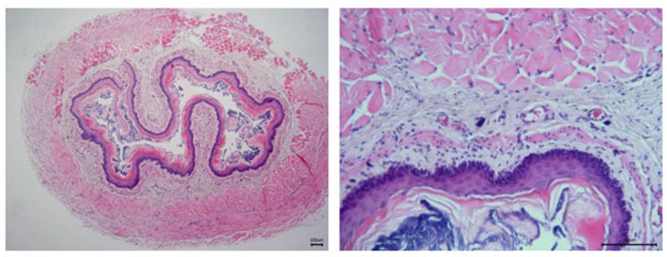

大鼠食管组织HE染色:对照组

- 组织学检查可观察食管黏膜的病理变化,如炎症浸润、细胞增生等。